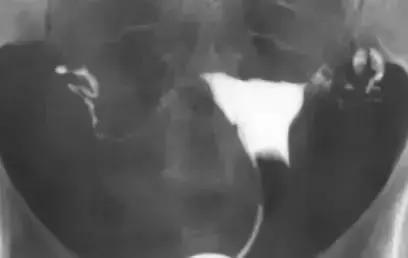

宫腔粘连